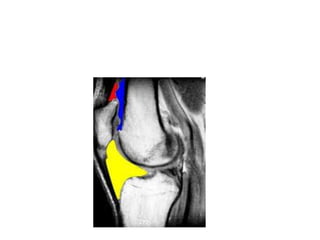

Menisci

• Tibio-femoral congruence is improved by the medial and

lateral menisci, forming concavities into which the femoral

condyles to sit.

• Important role-

1.distributing weight-bearing forces.

2. reducing friction

3. serving as shock absorbers.

The medial meniscus is C-shaped,

whereas the lateral meniscus forms

four fifths of a circle.

Role of the menisci

• The strong attachment to the menisci prevent them from

being squeezed out during compression of tibial femoral joint.

• Allowing greater contact area between menisci &femur

• If femoral condyle sat directly on the relatively flat tibial

plateau,there would be little contact ,between bony surfaces.

• With the addition of the menisci ,the contact at the

tibiofemoral joint is increased and joint stress (force per unit

area)reduced on the joint articular.